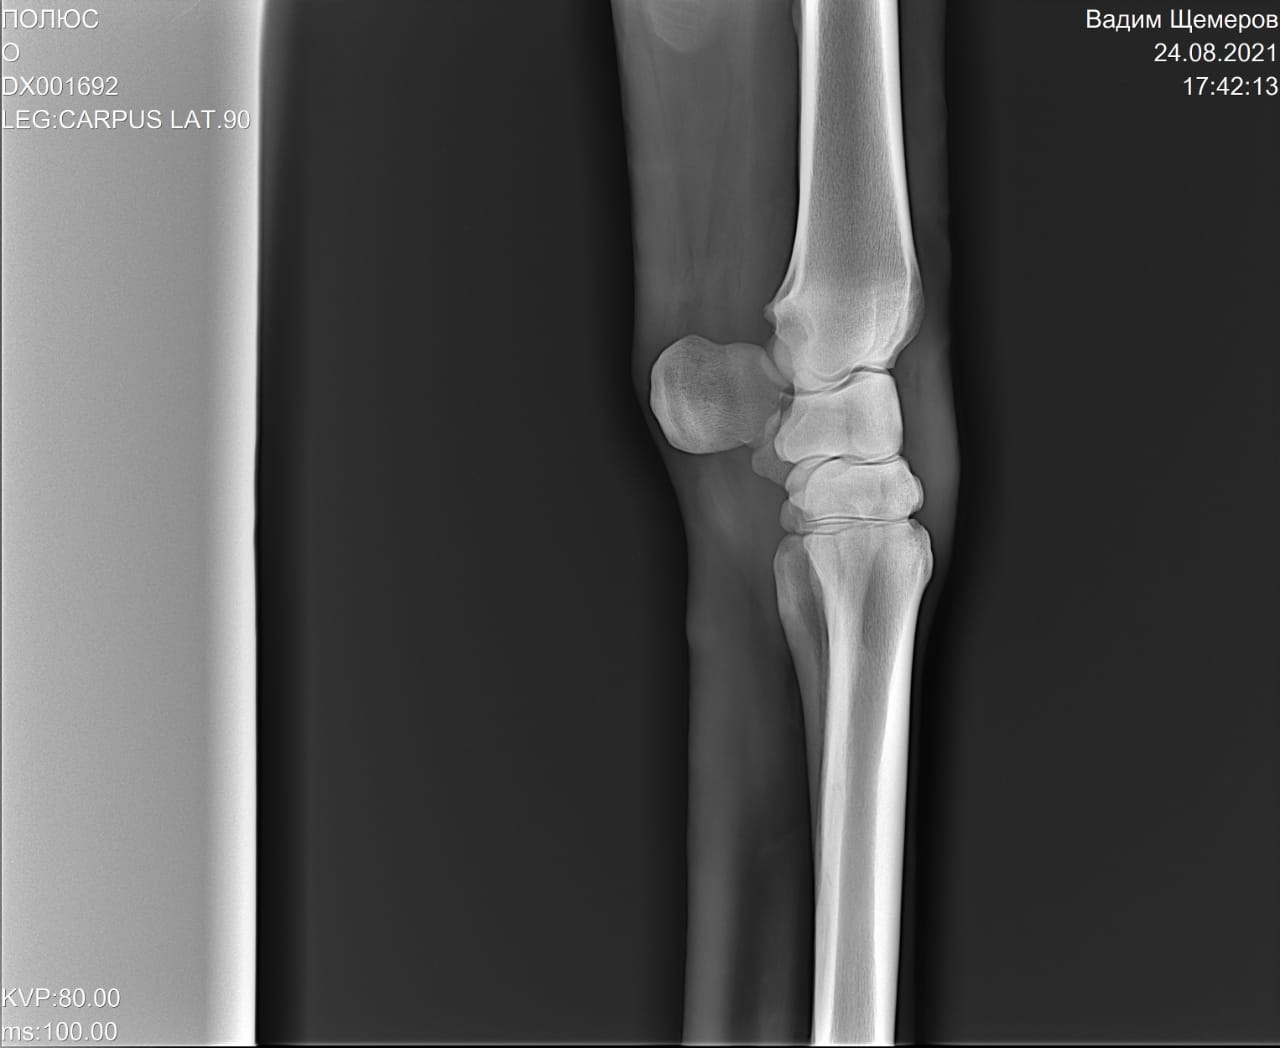

На рентгеновских снимках выявлено:

1) остеохондроз и чип в области путового сустава правой грудной конечности.